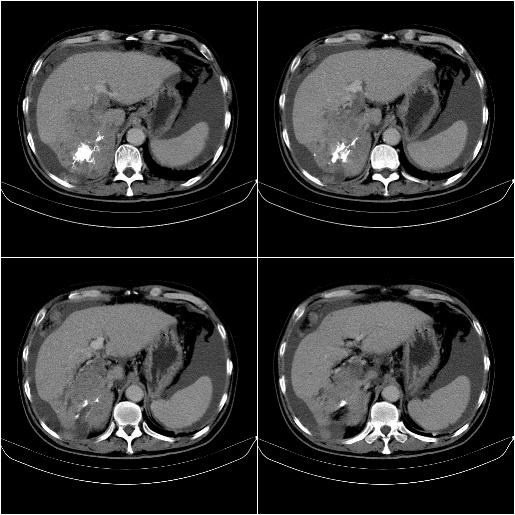

标题: CT21651:M,67Y,肝癌9月,介入术后3月。

m,67y,肝癌9月,介入术后3月。现腹胀、纳差、腹泻。

脾脏转移。。。

1)肝癌介入治疗术后碘油沉积不良。2)门静脉瘤栓形成,腹膜广泛性转移。3)肝硬化,脾大,腹水。4)慢性胆囊炎。